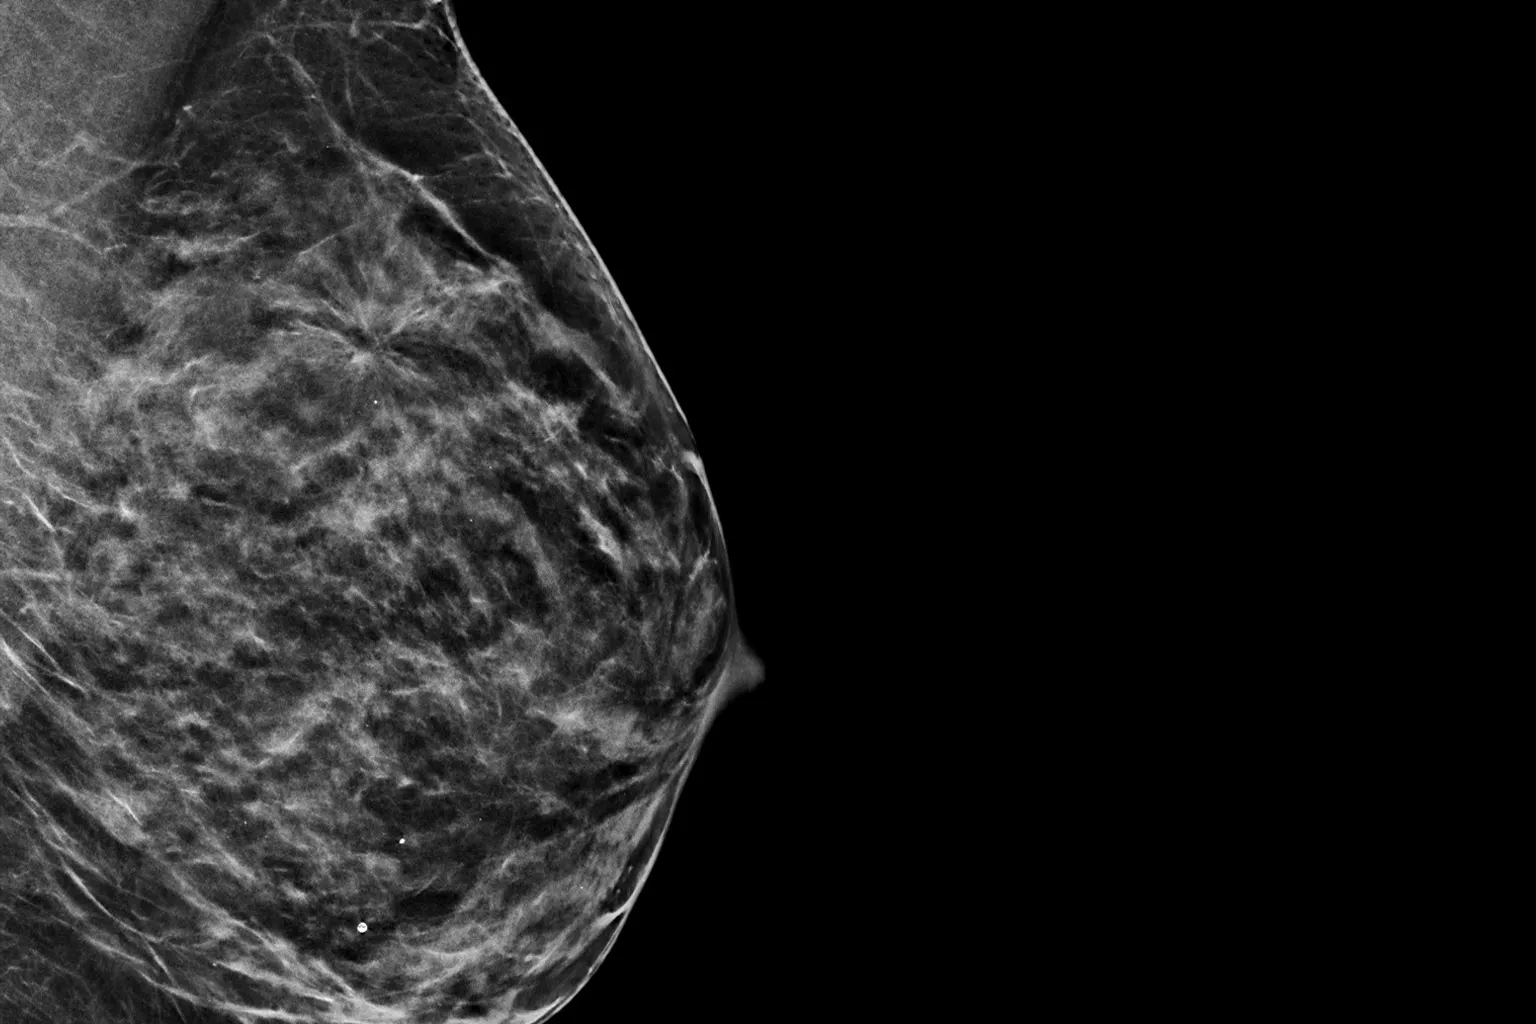

Raise your breast cancer screening performance1-4 with C-View software and instantly generated synthesised 2D images. It not only enhances details and speeds up the analysis, but also reduces radiation dose levels for your patients. C-View 2D images are clinically proven3,5 and FDA approved to diagnostically replace the FFDM images within a tomosynthesis screening exam.

C-View 2D images are clinically proven3,5 and FDA approved to diagnostically replace the FFDM images within a tomosynthesis screening exam. The images are also a navigational aid to the tomosynthesis slice review. Published studies show that the low dose 3D Mammography exam finds invasive cancer earlier, while also reducing false positive recall rates compared to 2D alone.4,5,7